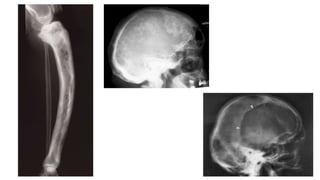

Multiple periosteal reactions

4) Hypertrophic pulmonary osteoarthropathy

Hypertrophic pulmonary

osteoarthropathy